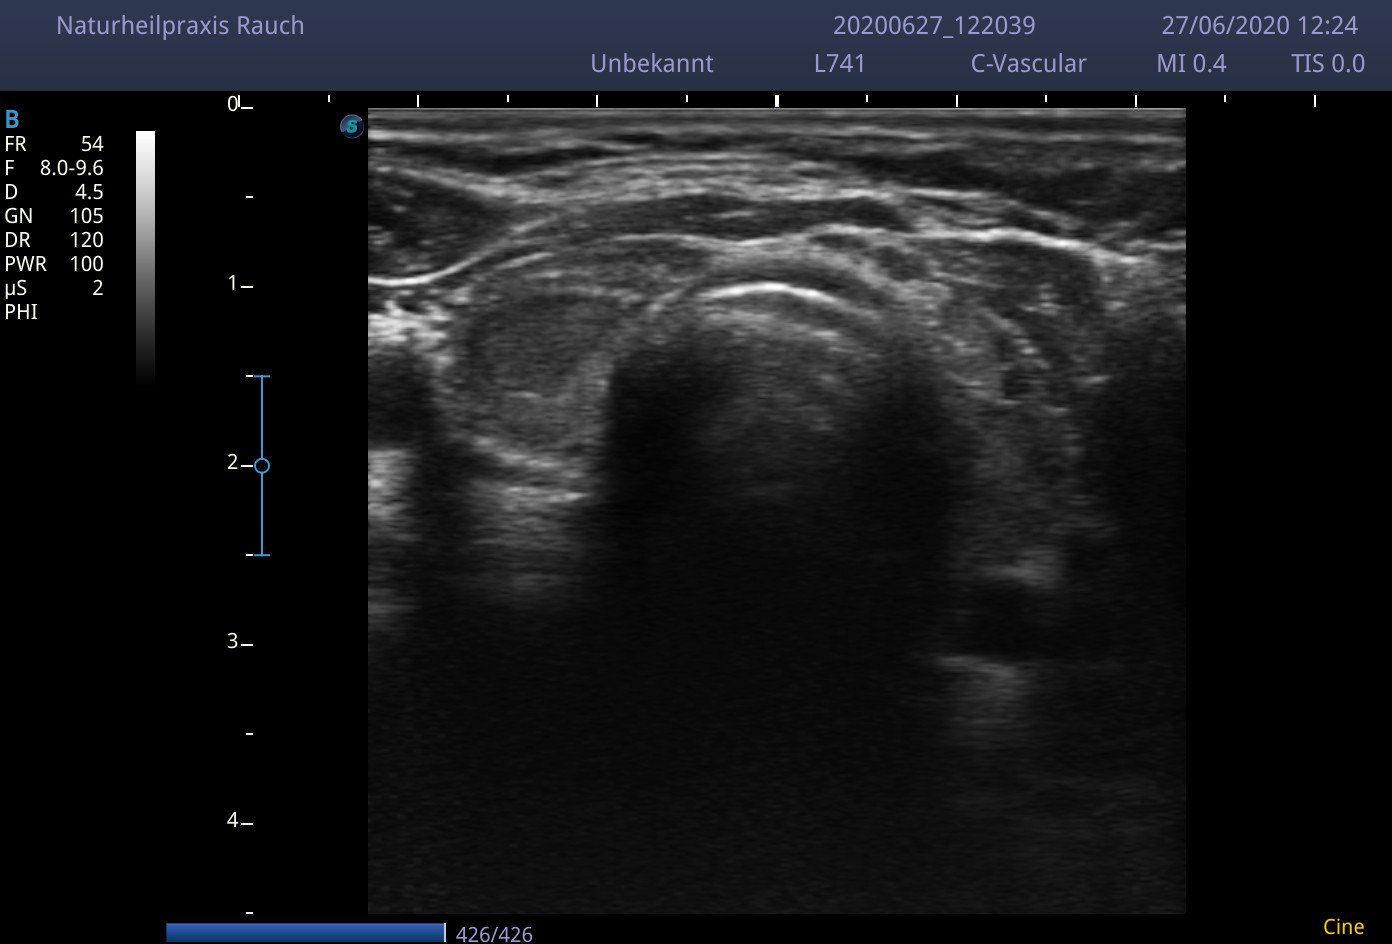

- der Schilddrüsen Ultraschall

Der Schilddrüsen Ultraschall und Ihre Körpertemperatur sind die wichtigsten Marker, für eine aussagekräftige Befundung Ihrer Schilddrüse. Sie zeigen Veränderungen des Schilddrüsengewebes bereits in einem sehr frühen Stadium an, wo das Blutbild noch keinerlei Veränderung sichtbar machen kann.